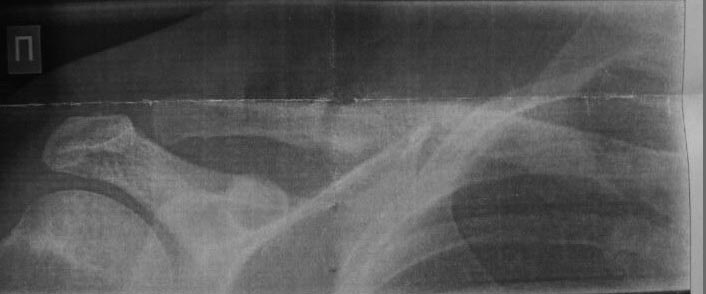

Добрый день. Сломал ключицу 02.2017. Оскольчатый перелом со смещением.

Была операция, остеосинтез спицей. Спицу достали 05.2017. Сделал контрольный ренген 24.07.2017. Прошу вашего мнения о снимке, так ренгенолог говорит о нормальном срощении, а хирург о наличии дефектов. Снимок прилагаю.

По одной проекции на плохого качества картинке можно уверенно сказать только то, что форма ключицы в этой проекции правильная. Так что надо ориентироваться в первую очередь не на картинку, а на клинические данные.